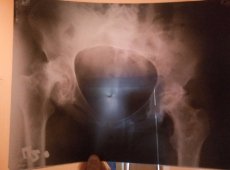

Лікарі поставили Христині страшний діагноз - асептичний некроз обох головок стегон з вираженою їх деформацією, дефектом кісткової тканини, з підвивихом кульшових суглобів догори 4-го ступеня, вторинні коксартрози обох тазостегнових суглобів 3-го ступеня, виражені артрогенні контрактури кульшових суглобів, виражений стійкий больовий синдром.

Стерся спочатку один, а тепер інший тазостегновий суглоб ноги. За висновком лікаря ортопеда єдиний варіант лікування - це ендопротезування в плановому порядку.